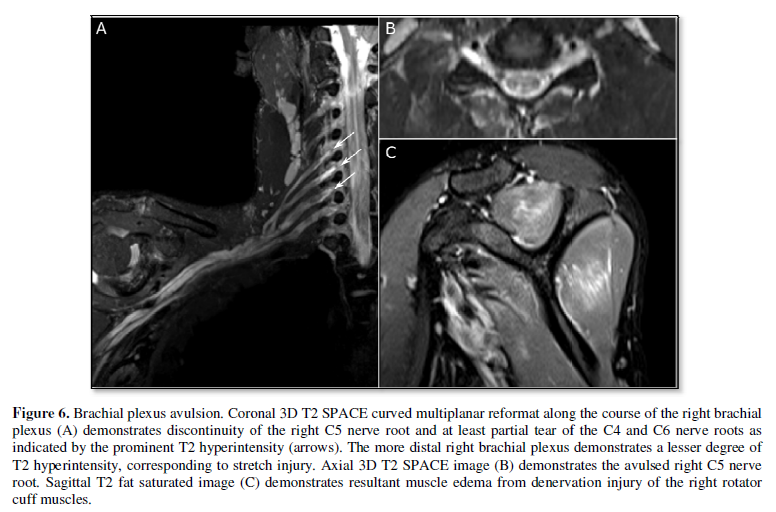

fascicles are either similar to or slightly brighter than skeletal muscle (Figure 4b). Nerve pathology often

initially presents as fascicular edema, indicated by T2 hyperintensity when

compared to other, uninvolved segments of the nerve or other regional

peripheral nerves. Occasionally, fascicular swelling can lead to

effacement of the perineurium and enlargement of the nerve. In some

neuropathies, individual fascicles may be abnormal, leading to varying sizes

and signal intensities of these fascicles. In cases of early myopathy from

nerve injury, the affected muscle also appears hyperintense on T2-weighted

imaging (Figure 6). The utility of

injury (Figure 5). Neurotmesis,

describes nerve disruption, which appears as discontinuity of the nerve on

imaging (Figure 6). Furthermore, injury involving specific groups

determined by clinical examination and electromyography. Although traditional

MRN has been limited to more proximal, larger caliber nerves, recent use of

high-resolution 3D techniques improves visualization of the fascicular

structure within nerves, allowing for more distal nerves to be imaged and permits

reconstructions in multiple planes [12], including along the plane of the nerve

(curved multiplanar reformatting; Figure

6).